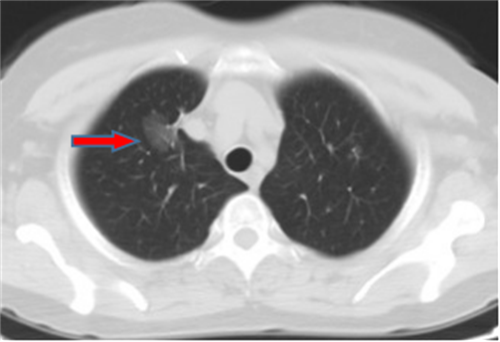

王女士,57岁,体检发现右下肺结节2月,术后病理诊断肺结节为肺隐球菌病。

李先生,45岁,发现右上肺结节2年,近期长大,术后病理诊断肺结节为炎性假瘤。

龙先生,65岁,体检发现右下肺结节,术后病理诊断肺结节为硬化性血管瘤。

郭女士,63岁,体检发现右下肺结节20天,术后病理诊断肺结节为浸润性腺癌。

王女士,65岁,体检发现右上肺磨玻璃结节16天,术后病理诊断肺结节为浸润性腺癌。

王女士,52岁,体检发现右上肺磨玻璃结节7月,术后病理诊断肺结节为原位腺癌。

王女士,35岁,新冠核酸检查阳性7天,胸部CT检查左上肺磨玻璃影,考虑新冠病毒性肺炎。